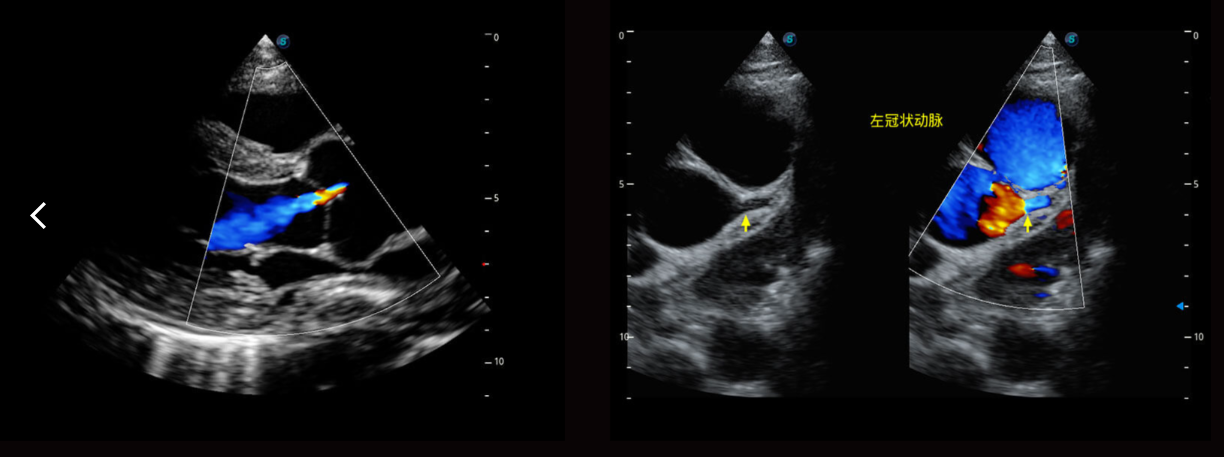

Các công nghệ siêu âm tim mạch cao cấp:

Phân tích định lượng cơ tim (MQA): Đo lường định lượng chính xác về cơ học cơ tim đạt được bằng MQA dựa trên theo dõi chuyển động thành nhạy cảm theo thời gian thực. Nó cung cấp đánh giá toàn cầu và khu vực bao gồm biến dạng, tốc độ biến dạng, dịch chuyển, vận tốc, v.v.

Siêu âm tim gắng sức Stress Echo

LVO: Các khả năng nâng cao của S50 Elite cho phép làm mờ thất trái trong quá trình kiểm tra gắng sức để tăng cường khả năng phân biệt giữa mô cơ tim và nhóm máu, cung cấp hình ảnh tốt hơn về màn hình viền nội tâm mạc, đặc biệt đối với những bệnh nhân khó.